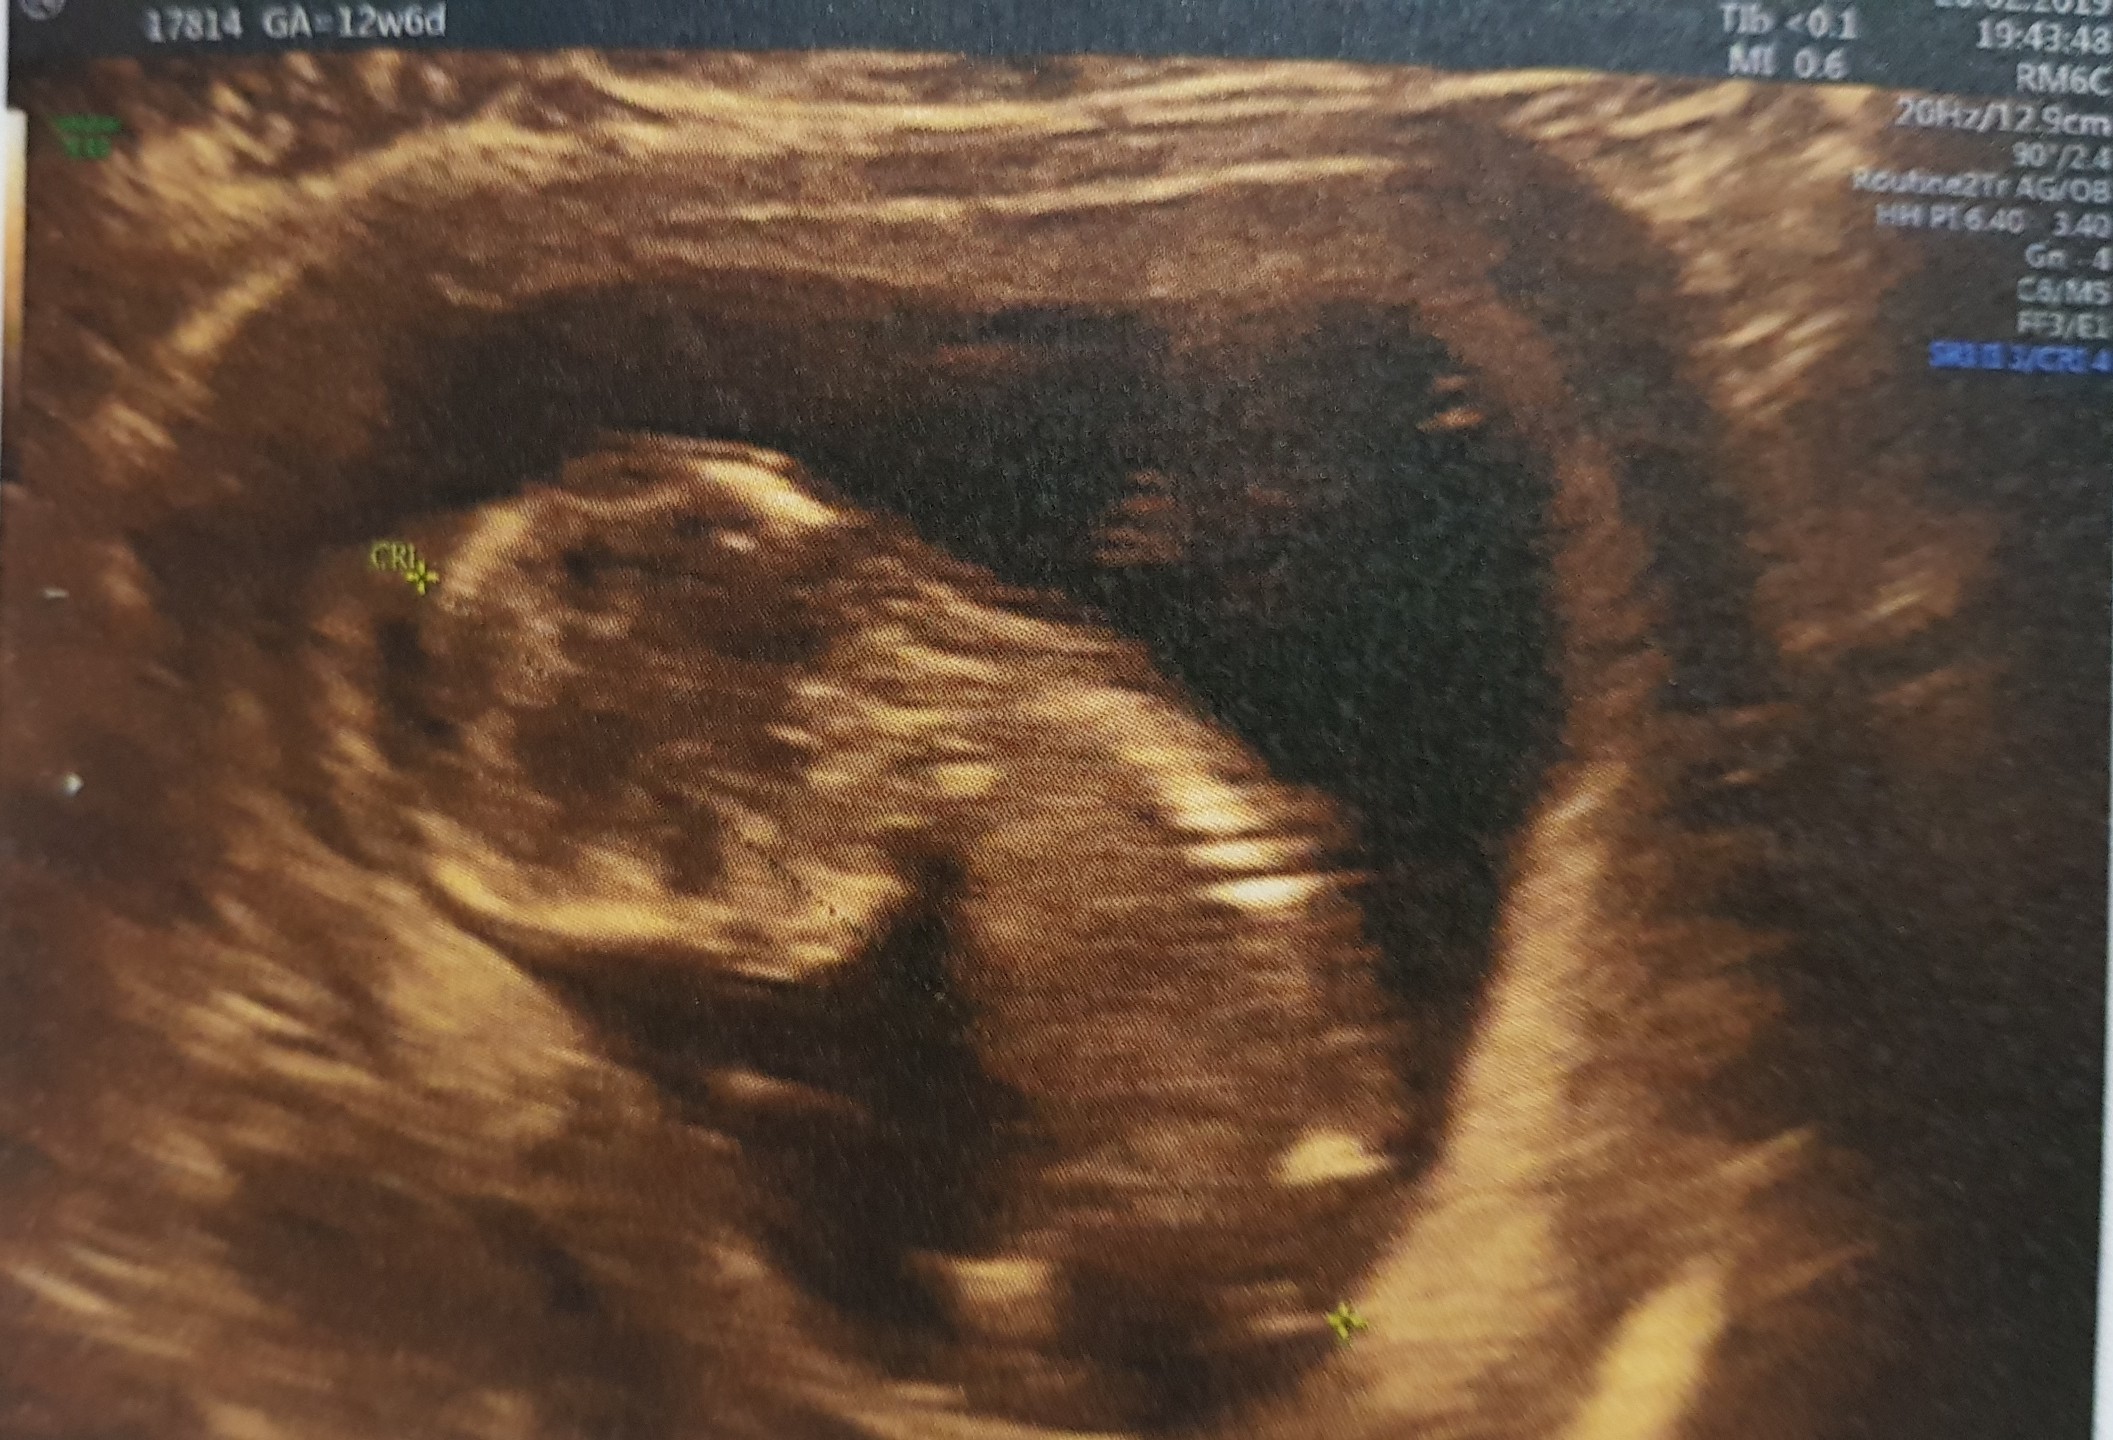

My po prenatalnych, 12t6d. Dzidzia ma 6,9cm. Wszystkie pomiary wyszły dobrze, w normach. Niestety płci maleństwo nie odkryło przed nami :)

• 20190220_213612.jpg

20190220_213612.jpg

608,1 KB · Wyświetleń: 112